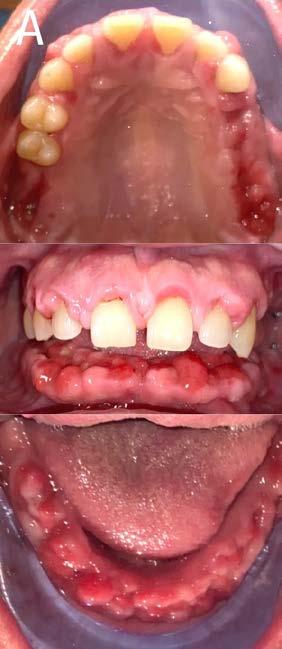

Figura 1. Fotografías intraorales: a) arcada superior, b) oclusión lateral derecho y c) oclusión central, d) oclusión lateral izquierdo y e) arcada inferior.

Al examen intraoral se observa arcada dental incompleta; con ausencia de órganos dentales 16 y 27 (Figura 1).

Figura 3. Fotografías intraorales.

hace 8 años por lo que toma 30 mg de nifedipino cada 12 horas, amlodipino 5 mg cada 24 horas, telmisartan 40 mg cada 12 horas y metropolol 100 mg cada 12 horas, además comenta padecer diabetes mellitus tipo II desde hace 7 años por lo que también toma 50 mg de metformina cada 12 horas y dapagliflozina 10 mg cada 24 horas. Clínicamente se observó una encía roja y sangrante, profundos sondeos, una notable hiperplasia gingival, depósitos de cálculo y movilidad dental grado III en todos los órganos dentarios a excepción del segundo premolar superior derecho al canino superior izquierdo, quienes presentaban una movilidad grado II. Radiográficamente se encontró una pérdida de inserción radiográfica avanzada generalizada

(Figura 2). Por lo que se diagnostica con periodontitis generalizada, estado IV, grado C (Figura 3).